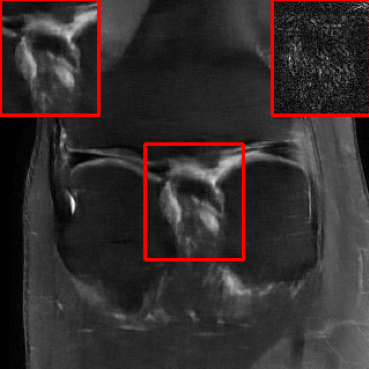

Results for the DIDN-based Reconstructor: To demonstrate adaptability to different network architectures, Table II compares reconstruction performance on the test set with the DIDN denoiser-based MoDL architecture. Average PSNR values with LONDN-MRI are compared to those with networks trained globally at different training set sizes. We ran only iteration of LONDN-MRI, where the reconstruction with a pre-trained (global) network was used to find neighbors. PSNR values for the oracle LONDN-MRI reconstructor are also shown. The overall performances with the DIDN-based architectures are better than with the UNet-based unrolled networks. The PSNRs for LONDN-MRI are consistently and similarly better than for the globally trained network across the different training set sizes considered, indicating potential for LONDN-MRI in improving state-of-the-art models. Fig. 6 visually compares reconstructions and reconstruction errors (in zoomed in region) for different methods. We can see that the LONDN reconstructors capture the original image features more sharply and accurately than the globally learned reconstruction.

| Ground Truth | Global | LONDN-MRI | Oracle |

| (1 iteration) | |||

![]() |

| PSNR = dB | PSNR = 34.15 dB | PSNR = 34.46 dB | PSNR = 34.54 dB |